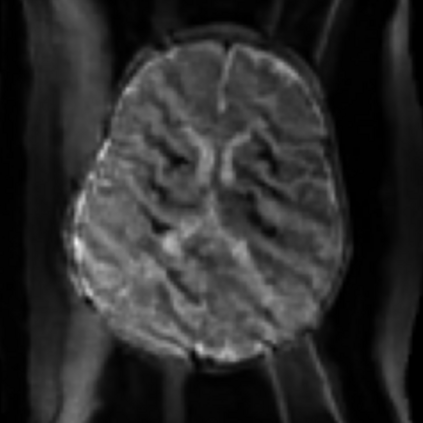

Assessing the severity of artifacts in pediatric brain Magnetic Resonance Imaging (MRI) is critical for diagnostic accuracy, especially in low-field systems where the signal-to-noise ratio is reduced. Manual quality assessment is time-consuming and subjective, motivating the need for robust automated solutions. In this work, we propose BRIQA (Balanced Reweighting in Image Quality Assessment), which addresses class imbalance in artifact severity levels. BRIQA uses gradient-based loss reweighting to dynamically adjust per-class contributions and employs a rotating batching scheme to ensure consistent exposure to underrepresented classes. Through experiments, no single architecture performs best across all artifact types, emphasizing the importance of architectural diversity. The rotating batching configuration improves performance across metrics by promoting balanced learning when combined with cross-entropy loss. BRIQA improves average macro F1 score from 0.659 to 0.706, with notable gains in Noise (0.430), Zipper (0.098), Positioning (0.097), Contrast (0.217), Motion (0.022), and Banding (0.012) artifact severity classification. The code is available at https://github.com/BioMedIA-MBZUAI/BRIQA.